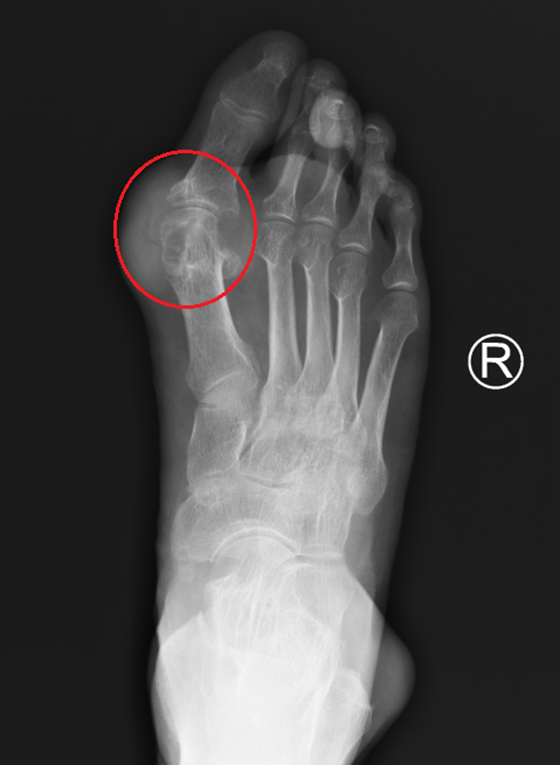

25岁年轻小伙杨某,本该是青春恣意的年纪,最近却饱受关节痛的折磨。自他15岁起关节肿痛彻底改变了他的生活。刚开始只是两只脚的大拇指又红又肿,摸上去特别烫,还非常疼痛,像有人拿刀子在割似的,后面小杨的膝盖、手都开始疼了,父母带去医院检查之后才发现小杨的血尿酸特别高,超过了700umol/l,看到结果,大家都吓了一大跳,医生最后给诊断了“痛风”!小杨父母都不敢相信,才十几岁的孩子,怎么就得痛风了呢?自此,痛风就伴随着小杨度过了漫长的青春期,疼痛也如影随形。甚至,小杨的手、脚都鼓起了包块,慢慢地长大。一开始,小杨还不以为意,可后来,脚上的石头越来越大,喜欢得鞋子都穿不了,手上的石头也在长大,灵活的手也像是被什么东西禁锢住了一般,变得笨拙。最痛苦的还是关节疼痛发作的时候,像在被人撕扯,恨不得没有这双脚才好。大家都说痛风是吃出来的,小杨觉得只要管住嘴就行,但是,不吃动物内脏,不喝酒,关节疼痛也还是没有放过他,尝试了很多方法,都不见特别好的效果。时间一长,小杨摸索出了一点规律,当他熬夜、喝碳酸饮料之后,关节痛肯定会发作,发作起来只能用止痛药去扛。渐渐地,小杨也不再抱有希望了,可能这辈子都会这样,再也摆脱不了它了。半个月前,小杨再次发作关节痛,吃了半个月的止痛药还是不见效,走路也一瘸一拐的,小杨的阿姨这才带他来到了湘雅常德医院风湿免疫科,找到了游运辉教授。经过系统的诊治后,小杨的关节肿痛终于得到了很好的控制,关节不红了,也不肿了,走路也没有太大的影响了。